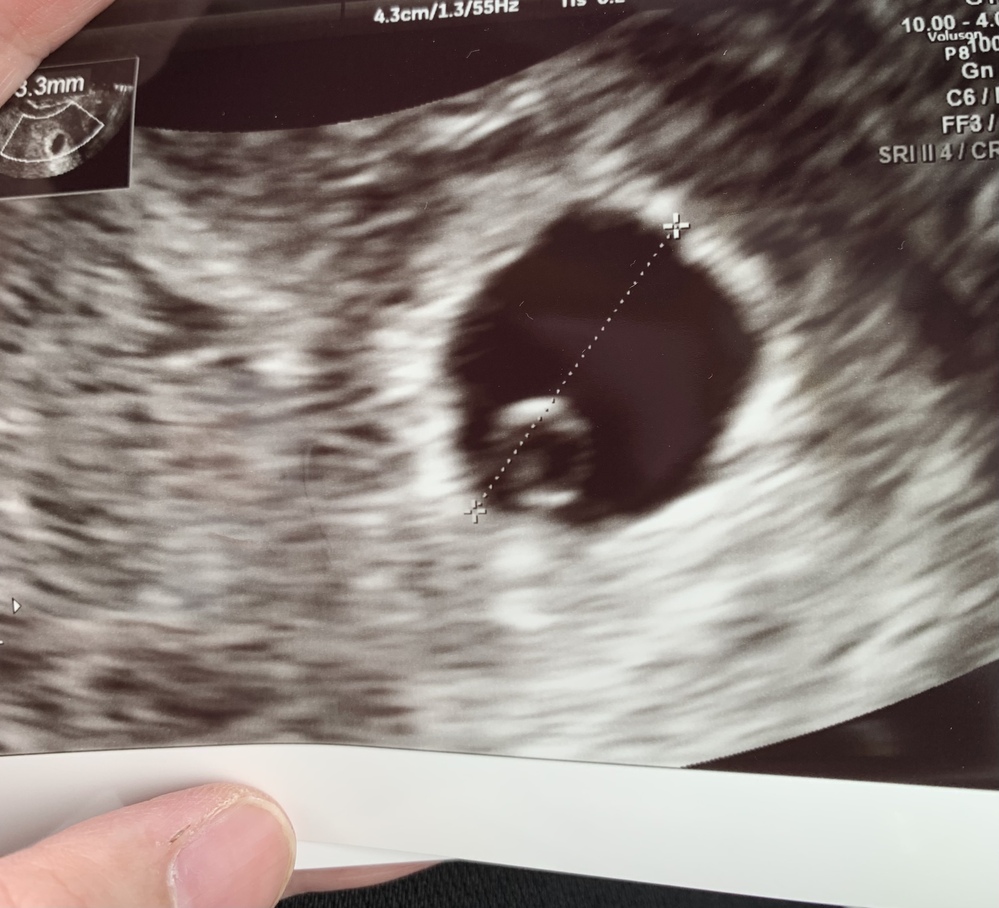

くろみつさんの妊娠6週目のエコー写真 心臓の動きが確認できてひと安心 エコー画像で振り返る、私に宿った小さな命が大きく育って誕生するまでの記録 おなかの赤ちゃんは元気でいるのかどうか不安だった2週間を経て、やっと検診の日が来ました妊娠4週になると見えてくる、「胎嚢」「卵黄嚢」って何? 妊娠5週になると脳や神経、心臓など臓器、それに手足や目、耳の原型もできるってホント? 妊娠6~7週で、心臓の動き出す!? まだ「胎児」と呼んでもらえない妊娠2ヶ月の「胎芽」時代の赤ちゃんのこと、母体のこと。 妊娠6週目は風邪のような症状 妊娠4週目、5週目と病院にいっていましたが、次回はgw明けに来てくださいといわれ、 急に診察が3週間ほど空くことになり不安度はmax。 具合悪いほうがよく育っているというわけでもないらしいんだけど、症状が軽いとそれはそれで不安

妊娠6週目 エコー写真 胎芽や胎嚢大きさ 心拍確認や気になる流産 妊娠初期 All About

医師監修 妊娠6週のエコー写真 心拍が確認できるころ マイナビ子育て

助産師監修 妊娠6週目 妊娠2ヶ月 エコー写真 心拍確認やつわり 出血について

妊娠6週4日 6w4d の超音波 エコー 写真